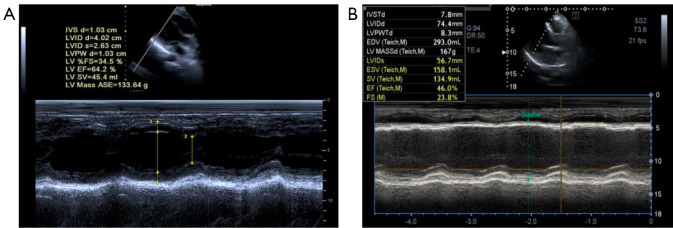

Methods: A total of 106 patients with AMI admitted to the Department of Cardiology of Hebei General Hospital between January 2023 and July 2024 were prospectively enrolled within 24 hours of symptom onset. Indicators including circulating miRNA-29b levels [detected via real-time quantitative polymerase chain reaction (RT-qPCR)], myocardial enzymes, vascular endothelial growth factor (VEGF), and tumor necrosis factor-α (TNF-α) were assessed at baseline. Cardiac function was assessed by echocardiography. Left ventricular ejection fraction (LVEF), left ventricular fractional shortening (LVFS), left ventricular end-diastolic diameter (LVEDd), left ventricular end-systolic diameter (LVEDs), and left ventricular posterior wall thickness at end-diastole (LVPWd) and end-systole (LVPWs) were also measured. Based on echocardiography, patients with AMI (n=106) were divided into an abnormal cardiac function (ACF) group (LVEF <50%; n=50) or a normal cardiac function (NCF) group (LVEF ≥50%; n=56). Thirty healthy participants were selected as the control group. Variables were compared with independent samples t-tests. Correlation and receiver operating characteristic (ROC) curve analyses were also conducted.